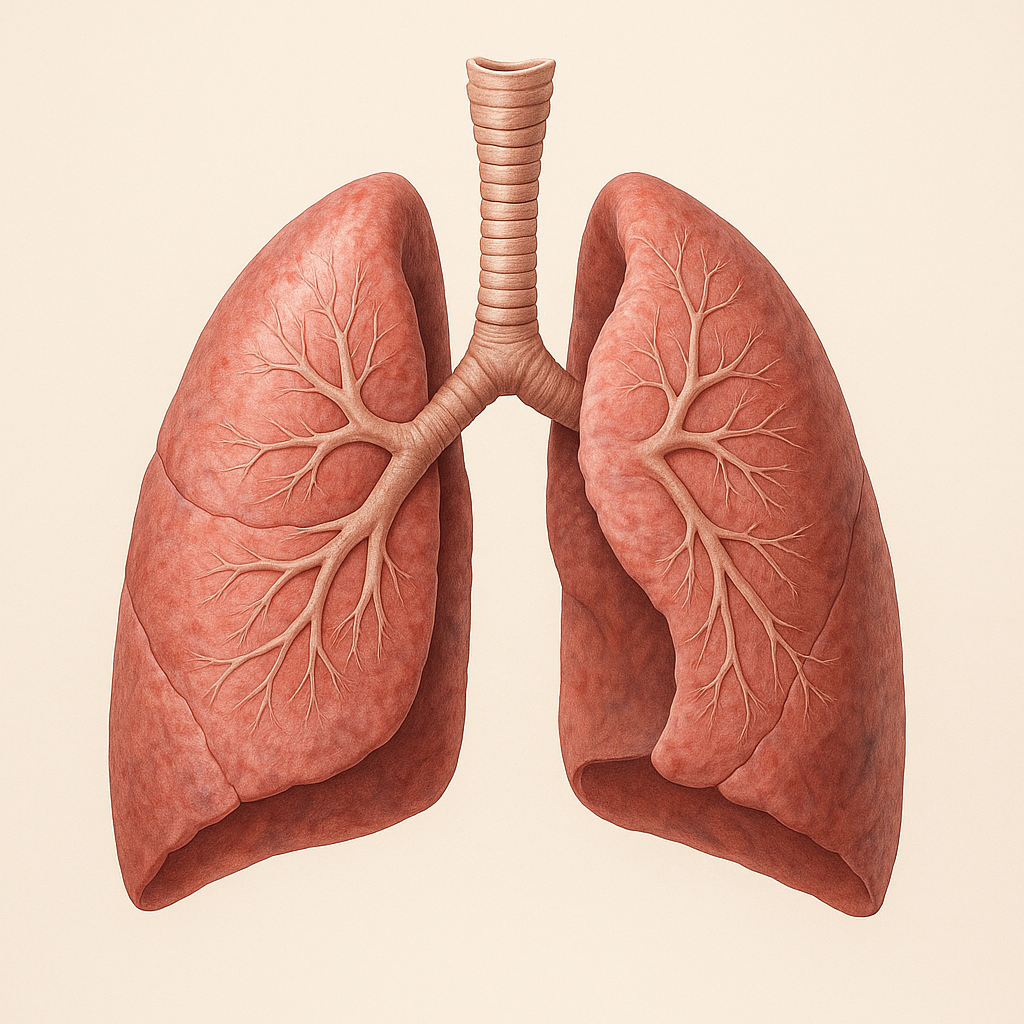

Indoor air pollution from gas stoves is an underrecognized but significant threat to children’s lung health in U.S. apartments—especially during winter, when homes are tightly sealed and ventilation is limited.

Gas stoves release nitrogen dioxide (NO₂), carbon monoxide, ultrafine particles, and formaldehyde, all of which can irritate developing airways and increase the risk of asthma, chronic cough, wheezing, and reduced lung growth in children.

Children, whose lungs are still developing, are particularly vulnerable. Over the past decade, evidence has grown that gas stoves are not just a climate issue—they are a child respiratory health issue, especially in winter.

Children’s Lungs Are More Vulnerable Than Adults

Children are not just “small adults.” Their respiratory systems differ in ways that increase susceptibility to indoor pollutants.

NIH-supported research shows that early-life exposure to NO₂ can permanently alter lung development, increasing the risk of asthma and reduced lung capacity later in life (NIH, 2022).

Lung Inflammation in Children

Nitrogen Dioxide and Airway Injury

NO₂ is a potent respiratory irritant. In children, it:

- Damages airway epithelial cells

- Increases mucus production

- Reduces lung defense against infections

Ultrafine Particles and Deep Lung Penetration

Ultrafine particles produced during gas combustion:

- Reach deep alveoli

- Cross into the bloodstream

- Trigger systemic inflammation

These particles are not captured by standard air quality monitors, making exposure invisible but biologically active.